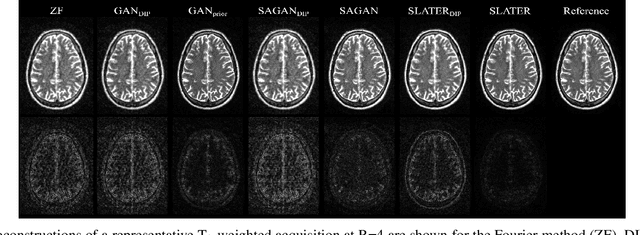

Abstract:Recent years have witnessed a surge in deep generative models for accelerated MRI reconstruction. Diffusion priors in particular have gained traction with their superior representational fidelity and diversity. Instead of the target transformation from undersampled to fully-sampled data, common diffusion priors are trained to learn a multi-step transformation from Gaussian noise onto fully-sampled data. During inference, data-fidelity projections are injected in between reverse diffusion steps to reach a compromise solution within the span of both the diffusion prior and the imaging operator. Unfortunately, suboptimal solutions can arise as the normality assumption of the diffusion prior causes divergence between learned and target transformations. To address this limitation, here we introduce the first diffusion bridge for accelerated MRI reconstruction. The proposed Fourier-constrained diffusion bridge (FDB) leverages a generalized process to transform between undersampled and fully-sampled data via random noise addition and random frequency removal as degradation operators. Unlike common diffusion priors that use an asymptotic endpoint based on Gaussian noise, FDB captures a transformation between finite endpoints where the initial endpoint is based on moderate degradation of fully-sampled data. Demonstrations on brain MRI indicate that FDB outperforms state-of-the-art reconstruction methods including conventional diffusion priors.

Abstract:Supervised deep learning has swiftly become a workhorse for accelerated MRI in recent years, offering state-of-the-art performance in image reconstruction from undersampled acquisitions. Training deep supervised models requires large datasets of undersampled and fully-sampled acquisitions typically from a matching set of subjects. Given scarce access to large medical datasets, this limitation has sparked interest in unsupervised methods that reduce reliance on fully-sampled ground-truth data. A common framework is based on the deep image prior, where network-driven regularization is enforced directly during inference on undersampled acquisitions. Yet, canonical convolutional architectures are suboptimal in capturing long-range relationships, and randomly initialized networks may hamper convergence. To address these limitations, here we introduce a novel unsupervised MRI reconstruction method based on zero-Shot Learned Adversarial TransformERs (SLATER). SLATER embodies a deep adversarial network with cross-attention transformer blocks to map noise and latent variables onto MR images. This unconditional network learns a high-quality MRI prior in a self-supervised encoding task. A zero-shot reconstruction is performed on undersampled test data, where inference is performed by optimizing network parameters, latent and noise variables to ensure maximal consistency to multi-coil MRI data. Comprehensive experiments on brain MRI datasets clearly demonstrate the superior performance of SLATER against several state-of-the-art unsupervised methods.